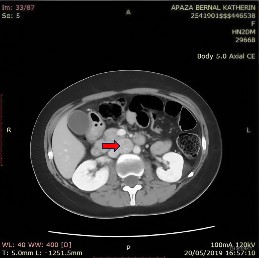

El diagnóstico anatomopatológico confirmó la sospecha de paraganglioma capsulado bien delimitado 2 x 1 x 0,3 cm, con bajo índice mitótico (<2), con resultado de inmunohistoquímica de cromogranina y la sinaptofisina positiva (Figura 3).

Figura 3 Examen anatomopatológico: paraganglioma capsulado bien delimitado de 20 x 10 x 3 mm